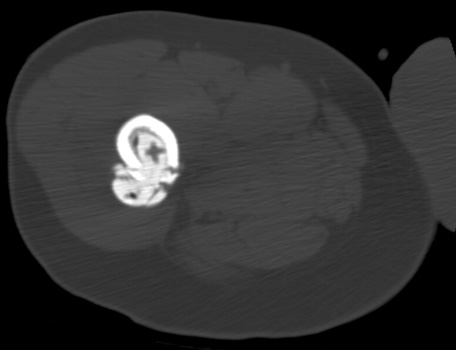

Cement extravasation in the pelvis from through defect in the

acetabulum.